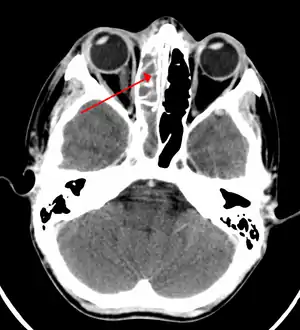

CT of chronic sinusitis

CT scan of chronic sinusitis, showing a filled right maxillary sinus with sclerotic thickened bone.